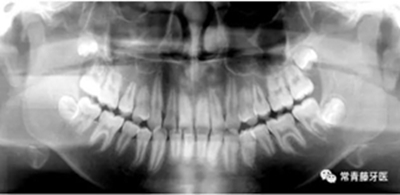

治療計(jì)劃

(1)直絲弓矯治器排齊上牙列,配合活動(dòng)腭桿擴(kuò)大上牙弓;

(2)上頜顴牙槽嵴植入種植釘,壓低上后牙,糾正開頜;

(3)拔除38、48,在下頜6、7間植入種植釘,整體遠(yuǎn)移下牙列。

治療過程

6個(gè)月,上牙列擁擠得到解除。上下頜植入種植釘,用于上后牙壓低及下牙列遠(yuǎn)移。

14個(gè)月,前牙開頜得到改善,配合使用垂直牽引。

16個(gè)月,前牙開頜糾正。

結(jié)束時(shí),可見前牙覆合覆蓋正常,上下牙列排齊,雙側(cè)尖磨牙達(dá)到中性關(guān)系。